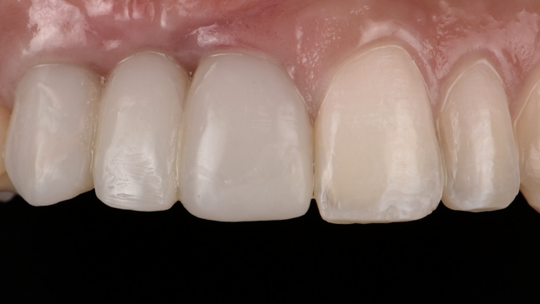

After the 3rd bone graft failed, the patient sought second opinions. She was a college sophomore at the time. Using a combination of interdisciplinary therapies, including S.M.A.R.T. minimally invasive bone grafting, Dr. Ernesto Lee was able to tridimensionally reconstruct this severe defect and place implants to restore the patient’s smile. The S.M.A.R.T. bone graft was also extended to treat adjacent teeth with thin/dehisced bone.

A long-term CAD/CAM fabricated temporary restoration is in place while she finishes medical school at an out-of-state university. The treatment of this case was published in detail in a special issue of the Compendium of Continuing Education in Dentistry, one of the largest circulation journals in our profession.